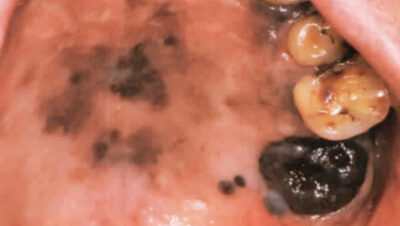

血腫

組織内で出血したものが固まってて、血の塊を作ったものです。血腫の原因

外傷、特に頬などを誤って咬んでしまったことなどにより、発現します。

いわゆる『血まめ』で、自然になくなりますので治療の必要はありません。

*血腫も大きものだと、このような状態になります。

出典元 クインテッセンス出版株式会社 『臨床で遭遇する口腔粘膜疾患に強くなる本』